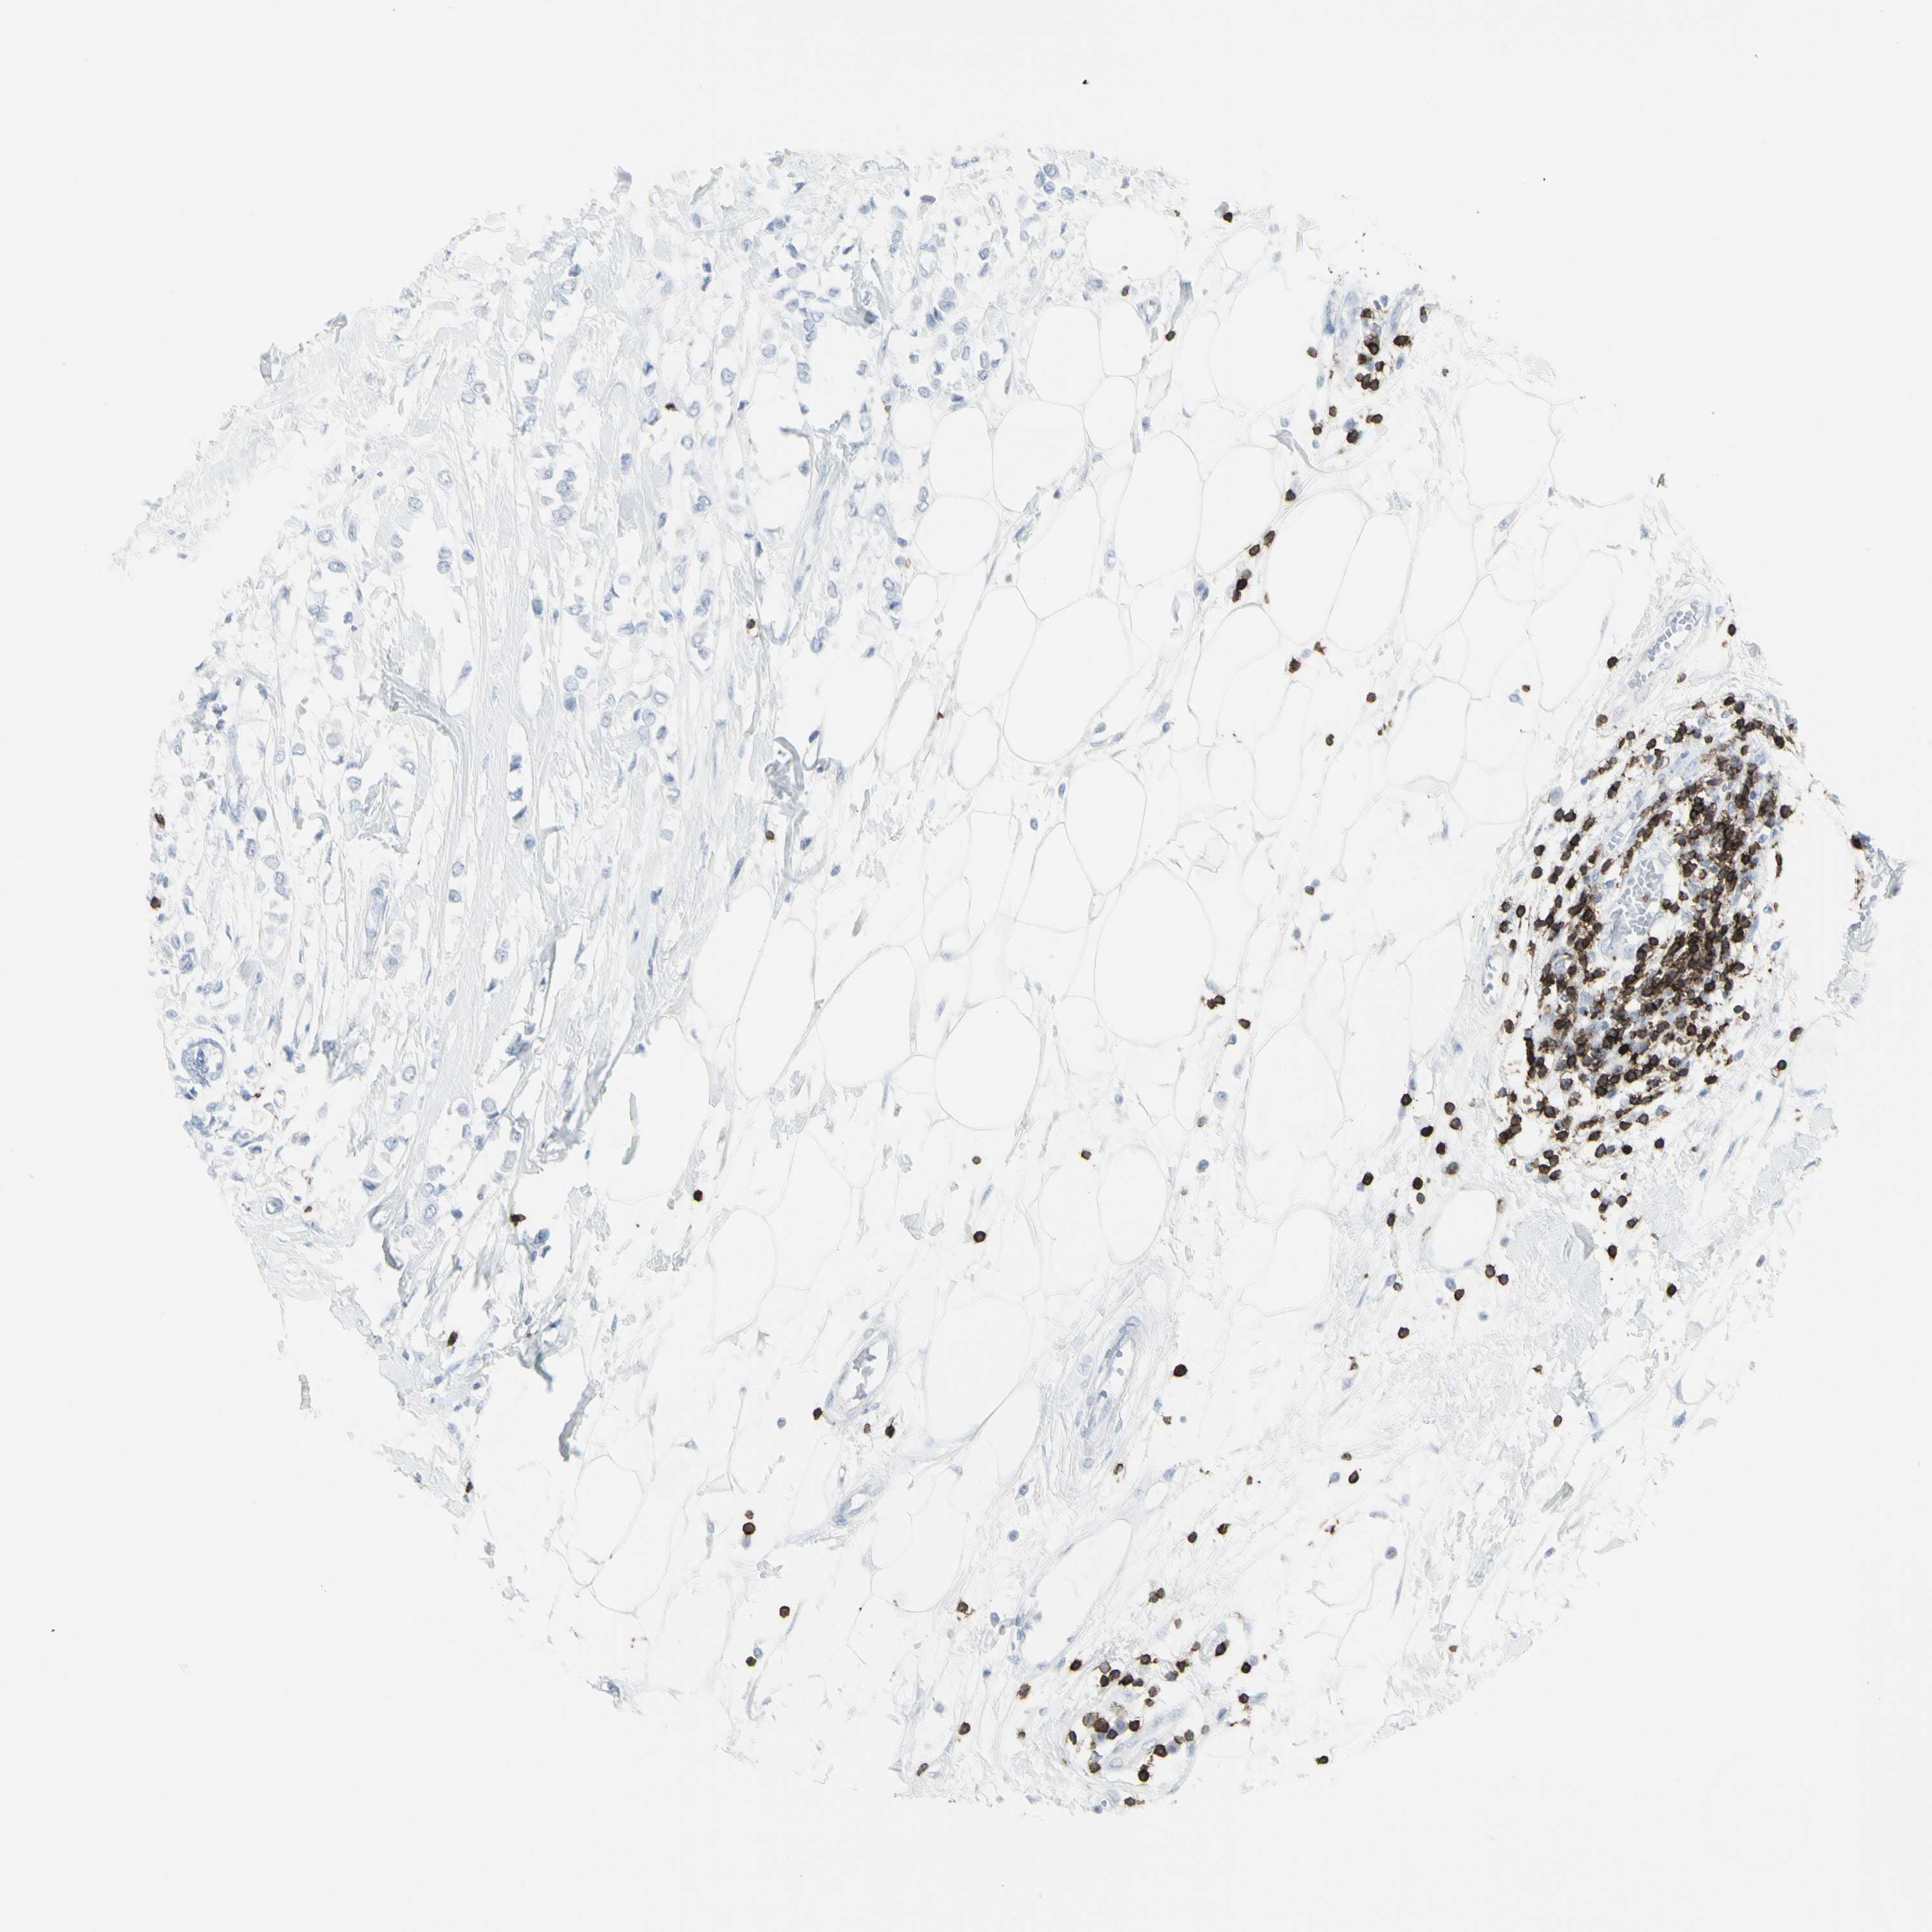

BRCA TCGA BRCA VALIDATION PROTEIN EXPRESSION

ANTIBODIES

AND

VALIDATION